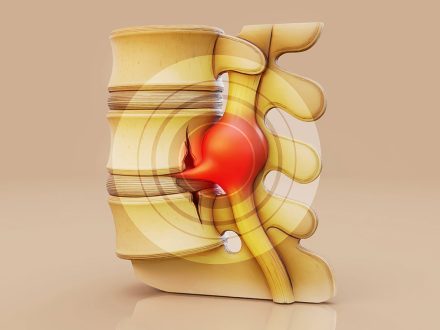

Endoskopik Bel Fıtığı Ameliyatı – Uzman Cerrah: Dr. Öğr. Üyesi Mehmet Akif Çaçan Bel fıtığı, özellikle günlük yaşamı ciddi şekilde

Endoskopik Boyun Fıtığı Ameliyatı – Uzman Cerrah: Dr. Öğr. Üyesi Mehmet Akif Çaçan Boyun fıtığı, omurga disklerinin boyun bölgesinde yer

Endoskopik Bel Fıtığı Ameliyatı İyileşme Süreci – Dr. Öğr. Üyesi Mehmet Akif Çaçan Bel fıtığı, günümüzde en sık görülen omurga